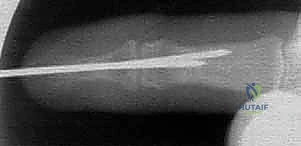

* Surgeon's Directive: "Once we've achieved and confirmed our reduction, we'll insert our second K-wire. This is a retrograde transarticular pin. Again, a 0.045-inch or 0.035-inch smooth K-wire."

* Technique: "I'm inserting this K-wire directly through the distal tip of the distal phalanx. We'll advance it in a retrograde manner, across the DIP joint, and into the middle phalanx. While advancing, ensure you maintain the reduced position of the DIP joint and the fracture. The pin should gain good purchase in the middle phalanx, ideally bicortical, to provide stable fixation."

TECH FIG 1 • D. With the DIP joint extended, a retrograde K-wire is introduced through the tip of the distal phalanx.

TECH FIG 1 • E. Once reduction is confirmed, this retrograde pin is advanced into the middle phalanx.

TECH FIG 1 • C. PA fluoroscopic image confirms good bony purchase in both the dorsal and volar phalanx.